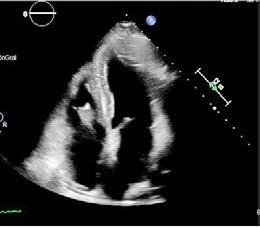

- Se realiza ecoscopia que describe ventrículo izquierdo no dilatado con FEVI (fracción de eyección del ventrículo izquierdo) conservada sin segmentarismos. Sin valvulopatías significativas. Ventrículo derecho normal. Aurícula izquierda ligeramente dilatada. Insuficiencia tricuspídea leve que permite estimar una PSAP (presión sistólica de arteria pulmonar) normal. No derrame pericárdico. Vena cava inferior ligeramente dilatada con colapso inspiratorio conservado.